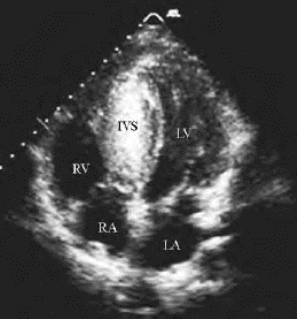

1.14.2第二节 二维超声心动图检查、测量方法及正常值

1.14.2.2二、常用切面图及用途